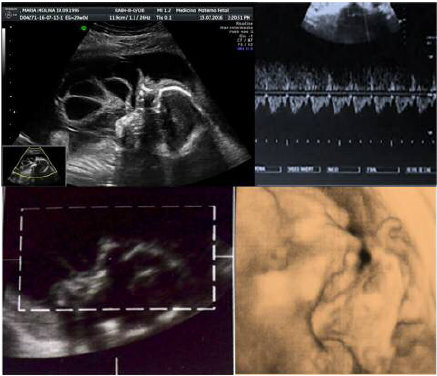

Paciente de 20 años de edad, procedente del estado Carabobo, de ocupación asistente administrativo, primigesta, con embarazo de 21 semanas, quien acude a la unidad de perinatología del Hospital materno-infantil “Dr. José María Vargas” para evaluación morfogenética del segundo trimestre. Sin antecedentes familiares y personales pertinentes, con un solo control prenatal para el momento de la evaluación. Se realizan estudios de laboratorio de rutina prenatal sin alteraciones y el cariotipo reporta feto 46 XY normal. El estudio ecográfico perinatal revela embarazo de 21 semanas con feto único, longitudinal, podálico, posición derecha anterior con imagen que emerge de cavidad bucal con aspecto ecomixto, lobulado (fig. 1, 2, 3) y polihidramnios con índice de líquido amniótico ILA P>95, planteándose como diagnósticos aparte de encefalocele anterior, épulis, epignatos, hamartomas entre otros tumores que protruyen a través de la cavidad oral. Resto del examen sin alteraciones. La finalización del embarazo se realiza por vía vaginal en la misma semana. En la autopsia perinatal se evidencia gran masa oral (fig. 4 y 5), con un componente quístico y sólido secundario debido al conducto esfenoideoccipital persistente. El contenido del encefalocele basal además de meninges y líquido cefalorraquídeo fue el lóbulo occipital, parte del tronco encefálico y la glándula pituitaria (fig. 6).